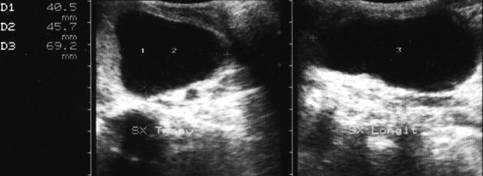

Pacienta de 28 ani. Voluminoasa tumefactie a lobului

stg., marcant hipoecogena, cu intarire posterioara, de 38x45x69mm.

La aspiratie, circa 60 cc de coloid foarte dens.